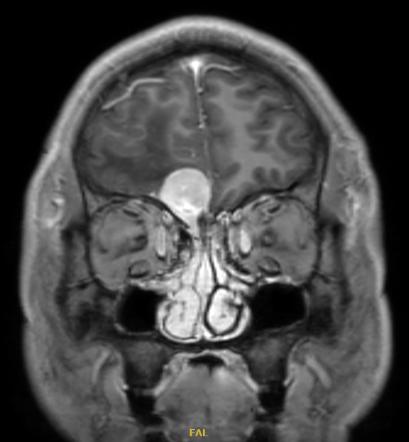

经查头颅CT、头颅核磁共振检查发现

刘先生右侧额头处有个肿瘤,还伴有大片水肿

结合刘先生丧失嗅觉多年的病史

“你之所以从小丧失嗅觉,是因为你打小靠近眼眶嗅沟处就长了个瘤子,它还在慢慢长大压迫你的脑组织,导致这次癫痫发作,不干预的话可能会脑梗塞、脑水肿,颅内压高导致瘫痪,必须尽快切掉!”

手术前